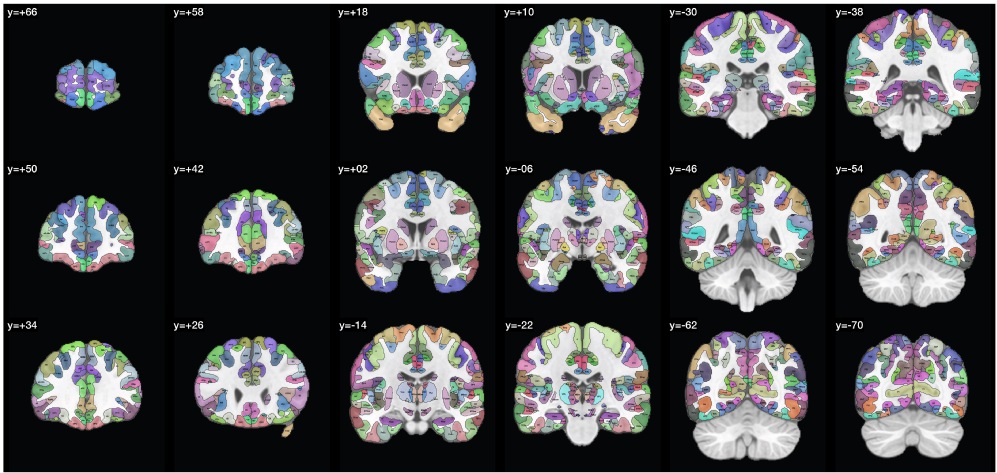

在原始的HCP-MMP1中,每一个区域有自身的区域代码,各个区域根据位置的接近性以及功能的相似性而进行分组,但这样的分组缺乏传统解剖学支持并容易造成理解上的困难。因此在HCPex中,参考亚利桑那大学的Dianne Patterson博士重新定义的皮层分区,将原始HCP-MMP1中的180个区域(每个半脑)根据神经解剖学定义重新排序,进一步形成22个主要的主要皮层分区(图1)。

图1 以体素为基础的皮层分区冠状位切面呈现

另外值得一提的是,本工作首次以冠状位切面呈现了HCP-MMP1的皮层定义以及HCPex在皮层下新增核团的空间定义,有益于神经科学研究者对于复杂模板定义的清晰了解。从图中可见,一些脑结构可以非常精细地显示以外,所有区域的定义都是严格紧贴灰质结构的,为未来更精细的脑功能研究提供更准确的定位标示。